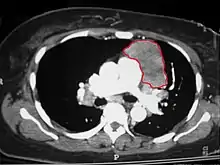

When a thymoma is suspected, a CT/CAT scan is generally performed to estimate the size and extent of the tumor, and the lesion is sampled with a CT-guided needle biopsy. Increased vascular enhancement on CT scans can be indicative of malignancy, as can be pleural deposits.[1] Limited biopsies are associated with a very small risk of pneumomediastinum or mediastinitis and an even-lower risk of damaging the heart or large blood vessels. Sometimes thymoma metastasize for instance to the abdomen.[5]